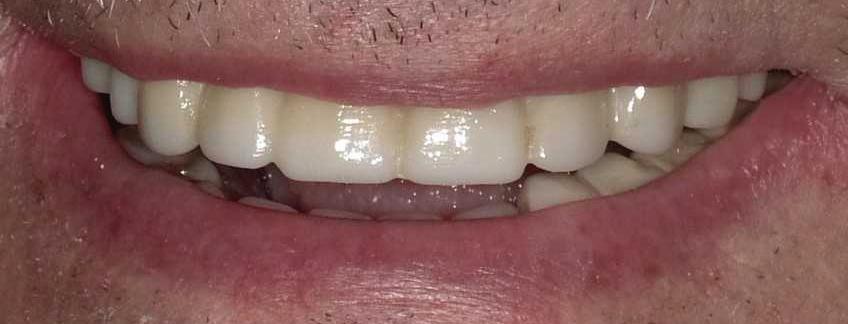

At Elite Prosthetic Dentistry, our “dream team” delivers an extraordinary blend of clinical precision and genuine care. Led by Gerald M. Marlin, D.M.D., M.S.D., a renowned specialist with over 3,700 successful implant procedures and a history of crafting crowns that last over 35 years, we are the trusted choice for adults seeking implant, cosmetic, and reconstructive dentistry in the Washington, DC metropolitan area. Why Choose Elite Prosthetic Dentistry?

• A warm, caring environment supported by a highly skilled team with an average tenure with us of 14+ years, complemented by oral and IV sedation protocols. With a commitment to advanced digital technology and artistry, Dr. Marlin works closely with each patient to deliver “simply radiant, simply natural” results. Our crowns last more than three times the national average, and our implants boast a >97% success rate over 20 years. Your journey to a revitalized smile begins here. Contact us today to schedule your consultation and experience the difference of truly exceptional dental care.